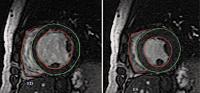

Abbildung 2: Kurzachsenschnitt in Höhe der Papillarmuskeln (links enddiastolisch = ED, rechts endsystolisch = ES). Epikard des linken Ventrikels und Endokard beider Ventrikel sind markiert